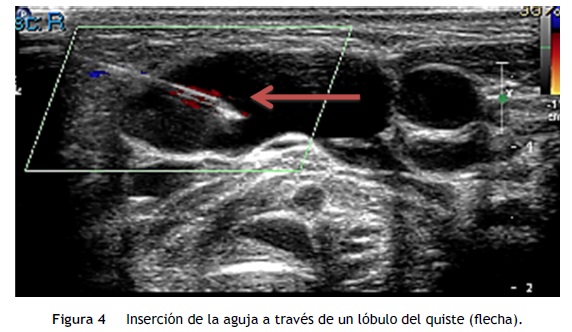

Por los hallazgos clínicos y radiológicos se solicitó interconsulta con Cirugía Pediátrica, quienes consideraron que no era candidata a la resección por la localización, extensión y compromiso de los órganos adyacentes. Ante el hecho de no ser candidata a cirugía, se buscó la opción menos invasiva. Con base en la experiencia del radiólogo pediatra en el manejo de este tipo de lesiones quísticas, se propuso la administración de etanol puro (100%) en infiltraciones de 0.5 a 1 ml en ocho sesiones, una cada dos semanas, con un procedimiento guiado por ultrasonido (fig. 4). Después de ocho sesiones, por medio de RMN se documentó la disminución del volumen del HQ y, como resultado, el incremento del espacio orofaríngeo y la liberación de una mayor área digestiva y respiratoria, que permitió una respiración autónoma y la alimentación por vía oral en la paciente.